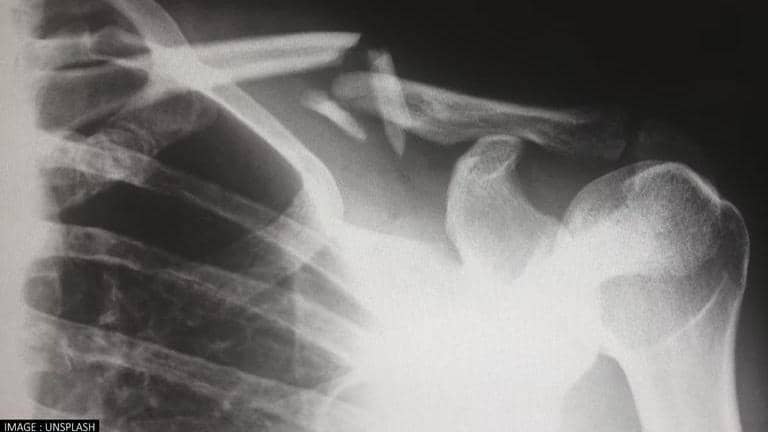

(Image: Unsplash)